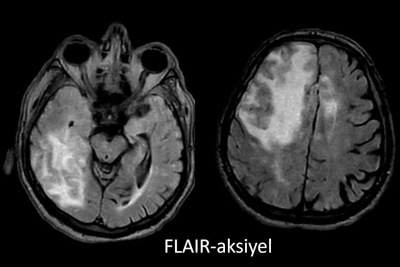

- A) Aksiyel planda FLAIR sekansta asimetrik kortiko-subkortikal vazojenik ödemi düşündüren yüksek sinyalli hafif ekspansil lezyonlar (turuncu ok).